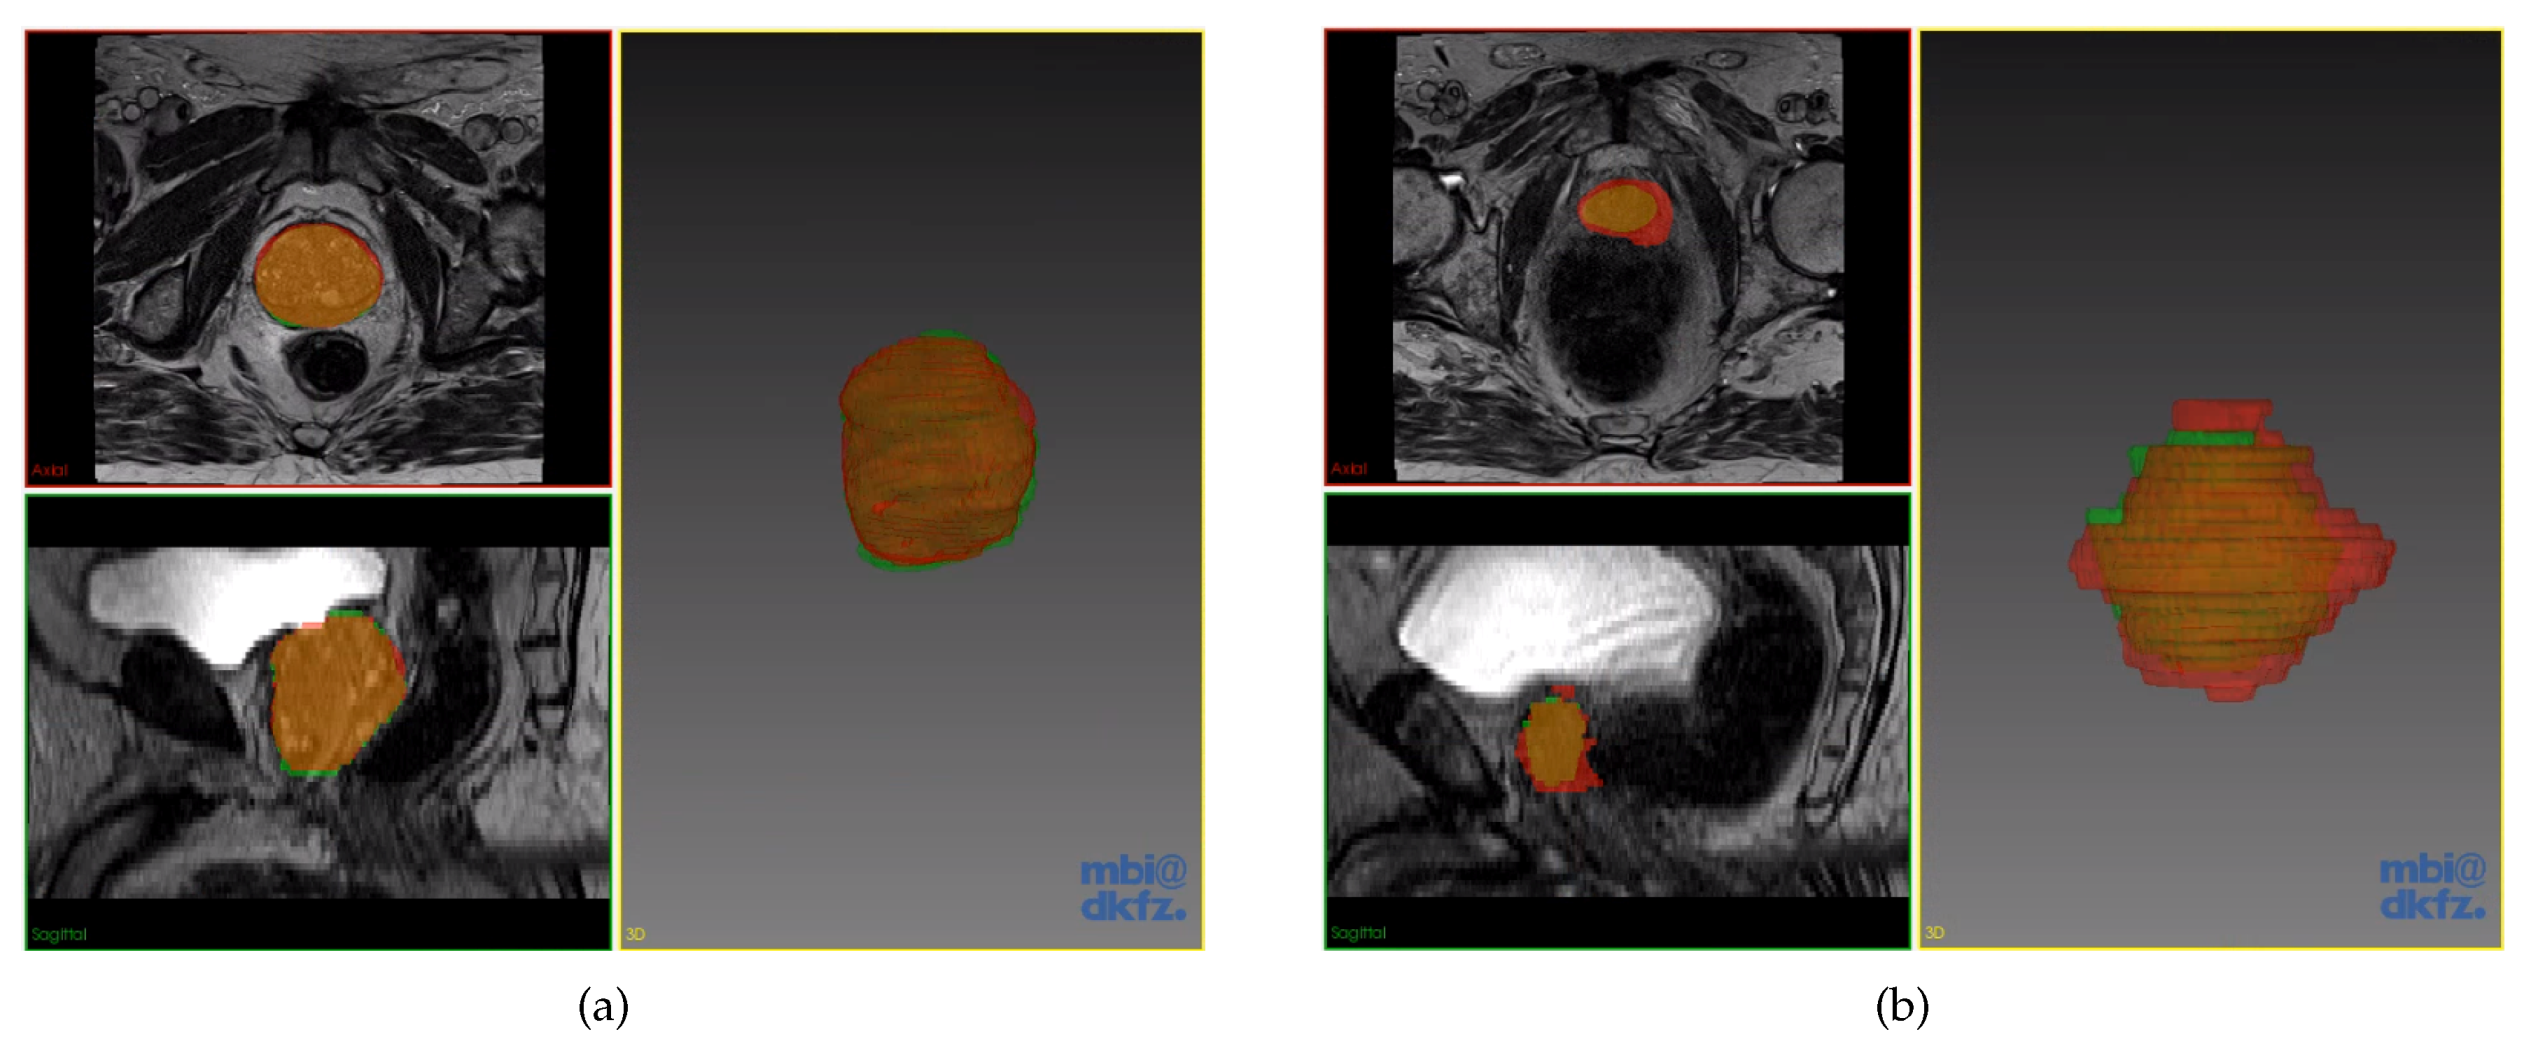

3.1. Dataset

4.1. Implementation on the Private Dataset

4.1.2. Results on the Private Dataset